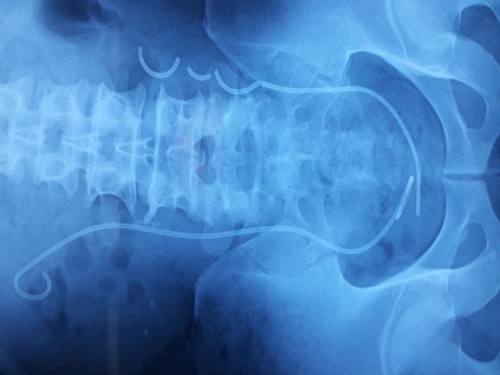

Hình ảnh chụp X-quang của bệnh nhân. Ảnh: PLO |

Theo thông tin từ báo Pháp Luật thành phố Hồ Chí Minh, vào ngày 18/3, BS-CK2 Phạm Thanh Phong - Phó Giám đốc chuyên môn Bệnh viện Đa khoa (BVĐK) Trung ương Cần Thơ, cho biết bệnh viện vừa thực hiện nội soi lấy ba đoạn ống thông JJ bị đứt trong niệu quản bệnh nhân D.H (56 tuổi, ngụ Hậu Giang).

Theo thông tin từ Zing, trước đó bệnh nhân D.H đến bệnh viện thăm khám vì tiểu ra máu kèm đau lưng. Bệnh nhân cho hay đã mổ sỏi thận cách đây hơn 3 năm tại TP.HCM, nhưng sau đó không đi tái khám theo lịch hẹn.

Sau khi kiểm tra, các bác sĩ kiểm tra phát hiện bệnh nhân còn ống thông JJ bên trái bị đứt thành 3 đoạn và còn có một sỏi niệu quản bên phải to khoảng 2cm.